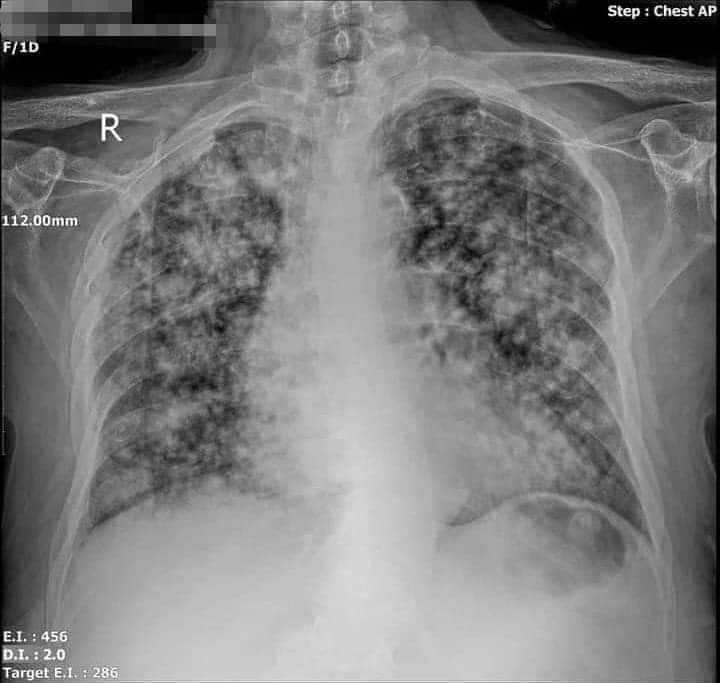

بعد ماروحت بعتولي الاشعه...المخ سليم لكن الصدر اكتر من ٨٠٪ منه مدمر تماما والمريض حاليا بالعنايه نرجو من الله له الشفاء.

After I did not receive the x-ray ... the brain is healthy, but the chest is more than 80% of it completely destroyed, and the patient is currently caring, we hope that God will recover him.